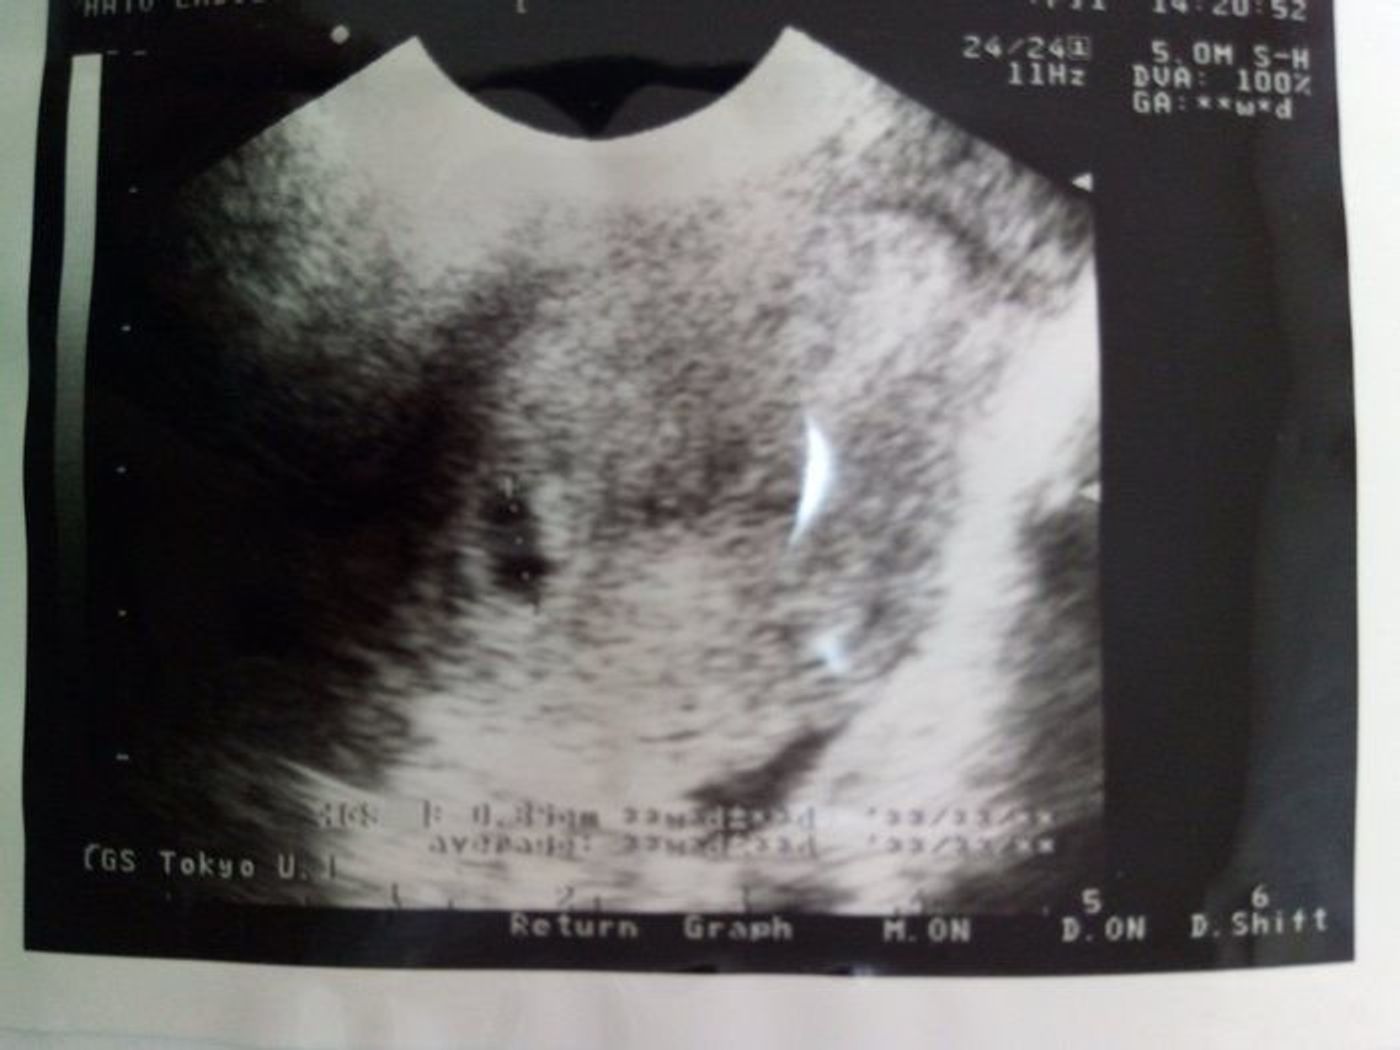

5 産科一般超音波検査 初期編 正常所見4 7週 日本産婦人科医会